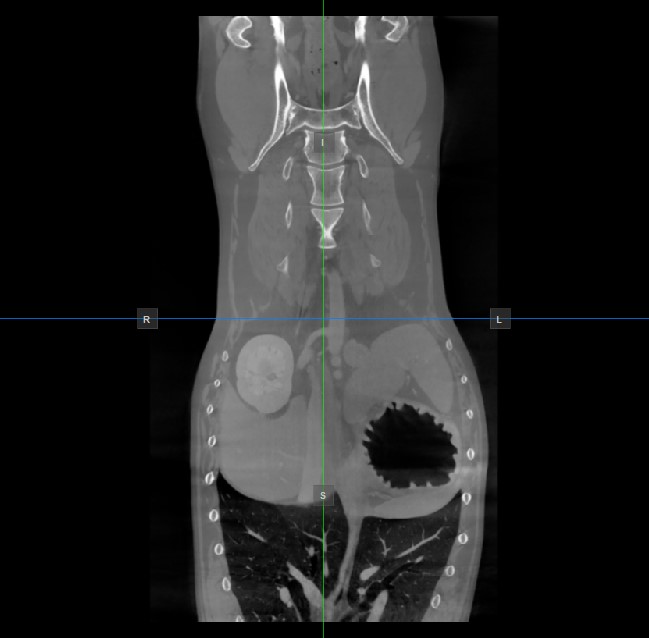

Image Orientation and Image Planes

The position and intersection of the other two image planes not represented in the active viewport is indicated by two vertical and horizontal lines called slicers. The endpoints of each slicer are labeled with a letter that corresponds to the appropriate direction/side of the 3D volume, based on the RAS coordinate system.

Only four sides of the available six are indicated on each 2D viewport. The labels and the corresponding side are the following:

• Patient Right (R), indicating the right side of the body

• Patient Left (L), indicating the left side of the body

• Anterior (A), indicating the front side of the body

• Posterior (P), indicating the back side of the body

• Superior (S), indicating the top side of the body

• Inferior (I), indicating the bottom side of the body

../../_images/image139.jpg